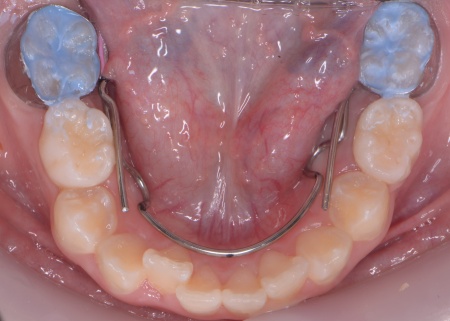

メリット デメリット また、治療にあたりお口全体のバランスを確認したところ口元の突出はなく、顎のサイズはやや小さめですが、成長期であることから歯列の拡大が可能な状態だと判断しています。 以上の内容について丁寧に説明し、治療に同意いただきました。 まず、上顎に顎の骨を広げるための固定式の矯正器具「急速拡大装置」を、下顎には歯並びの幅を広げるための「リンガルアーチ」を装着します。 次に歯の位置を整えるため、ワイヤー矯正を開始します。 最後に、歯並びが整って見た目や噛み合わせにも問題がないことを確認し、装置を取り外して第1期矯正治療を終了しました。 現在も経過観察を継続していますが、歯が元の位置に戻る後戻りも見られず、残っている乳歯から永久歯への生え変わりも順調に進んでいます。 |